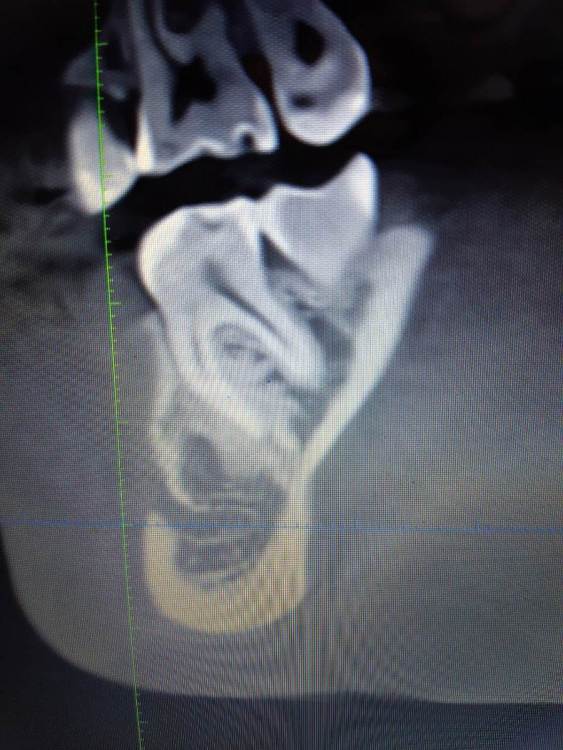

It'sGeorgy Опубликовано 15 января, 2020 Поделиться Опубликовано 15 января, 2020 Здравствуйте!На 2ом прикреплении явно следствие, на 3 и 4 - причина. Вижу 2 варианта развития событий:1: Разрезать, отслоиться. Посмотреть что явилось причиной, удалить причину. Начать готовить ложе под имплантат. 4.0 фрезой провалиться в полость кисты, попытаться извлечь ее через ложе. Поставить имплантат.2: Если через ложе извлечь не удастся, то пойти вестибулярным доступом. Извлечь. Графт, мембрана. 5 мес отдыха. Имплантат. Кто подобным уже занимался, подскажите, насколько перспективен первый вариант? Возможно ли по КТ понять что явилось причиной? На корень не особо похоже. Для остеомы тоже нетипичная картина. Ссылка на комментарий

shy Опубликовано 15 января, 2020 Поделиться Опубликовано 15 января, 2020 (изменено) резидуальная пошел бы через вестибулярный доступ , с графтом или без на усмотрение оперирующего . P.S причину уже удалили до Вас Изменено 15 января, 2020 пользователем shy 1 Ссылка на комментарий